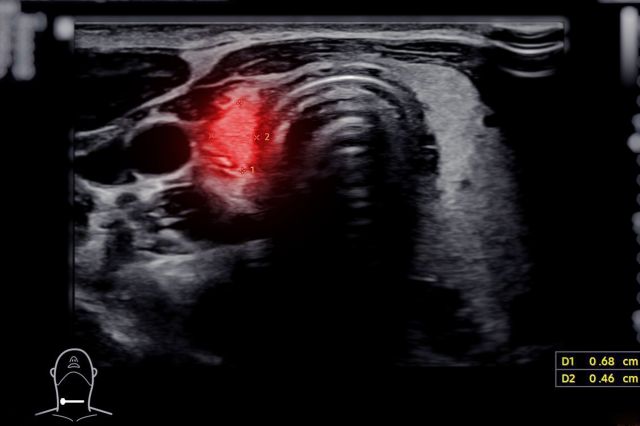

⑤副甲状腺腺腫、副甲状腺のう胞

甲状腺のしこりの鑑別として、甲状腺の背側にある副甲状腺の病気が挙げられます。正常の副甲状腺はエコーでは描出できませんが、腫瘍、のう胞などでは甲状腺のしこり、のう胞と鑑別を要します。

エコー所見では、上面は甲状腺被膜で隔たれていることを反映して白い線がみられます。副甲状腺のう胞では白い線が不明瞭なことがあります。